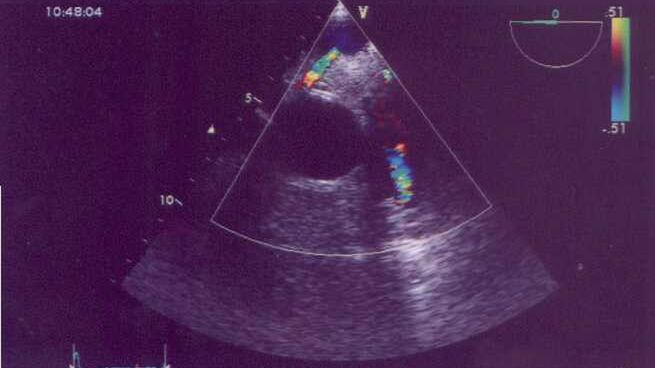

USG Alcapa